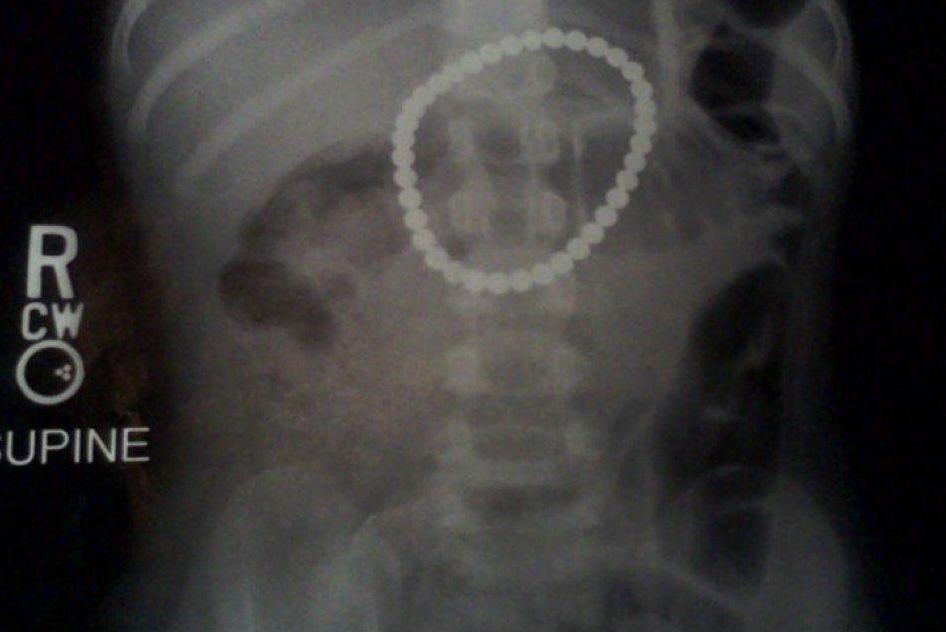

Неокуб (Buckyball) – очень опасная игрушка для детей. Изготавливается из сплава редкоземельного элемента неодима с железом и бором. Неодимовый магнит является одним из наиболее мощных. Сила сцепления — 400 гр, горстка шариков спокойно удерживает на весу молоток. Можно представить, с какой силой магниты притягиваются друг к другу, попав в кишечник ребенка

В такие кольца эти магнитные шарики соединяются, попав в кишечник ребенка, вызывая острую боль, рвоту, высокую температуру

Журналист Анастасия Ахметова столкнулась с опасностью, которую несут эти игрушки. Два месяца назад прооперировали ее двухлетнюю дочь, проглотившую 10 таких шариков. Это уже третья операция в этой клинике, когда из детей извлекают магниты«Неокуб». Когда полтора года назад она покупала для пятилетнего сына эту игрушку, на жестяной коробке не было никаких возрастных ограничений, продавец отдела «Умные игрушки» в «Детском мире» не сказала ничего об опасности, кроме того, что конструктор замечательно развивает моторику. Даже эта предупреждающая надпись, по мнению мамы пострадавшей девочки, не достаточно убедительна. «Уверена, что родители даже не подозревают о том, что эти мощные магниты могут притягиваться и внутри кишечника». После несчастного случая с дочерью, Анастасия выбросила все магниты, и для иллюстрирования темы фотограф нашел их в магазине игрушек. Надеемся, что после этого репортажа компания, импортирующая эту игрушку в Казахстан, разместит на своих промо-сайтах и интернет-магазинах возрастное ограничение и предостережет родителей от возможных тяжелых последствий

Хирург Булат Муратович, к которому девочка поступила в тяжелом состоянии, со всеми признаками непроходимости кишечника и перитонита, увидев на снимке цепь из металлических шариков, не сомневался – это магниты. После лапароскопии, когда через пупок ребенка был введен зонд, врач диагностировал перфорацию кишечника, и принял решение о немедленной полостной операции по удалению инородного тела. Лана провела 5 дней в реанимации, 10 дней в хирургическом отделении, полтора месяца ребенок был на строгой диете, сейчас девочка здорова

А это снимок трехлетней Пейтон Бушнелл, которая проглотила 37 магнитных шариков Buckyball. Родители девочки решили, что у ребенка болит живот, однако рентгеновский снимок продемонстрировал замкнутое ожерелье Buckyball в кишечнике маленькой девочки.